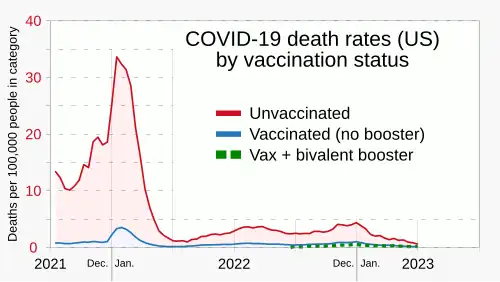

Knowledge about the structure and function of previous coronaviruses causing diseases like severe acute respiratory syndrome (SARS) and Middle East respiratory syndrome (MERS) accelerated the development of various vaccine platforms in early 2020.[209] In 2020, the first COVID‑19 vaccines were developed and made available to the public through emergency authorizations[210] and conditional approvals.[211][212] However, immunity from the vaccines wanes over time, requiring people to get booster doses of the vaccine to maintain protection against COVID‑19.[210]

The COVID‑19 vaccines are widely credited for their role in reducing the spread of COVID‑19 and reducing the severity and death caused by COVID‑19.[210][213] Many countries implemented phased distribution plans that prioritized those at highest risk of complications, such as the elderly, and those at high risk of exposure and transmission, such as healthcare workers.[214][215]